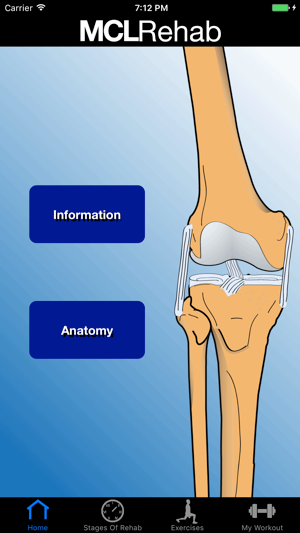

看更多 »MCL Rehab

The medical collateral ligament is one of the most common injures sustained of the knee. The MCL Reh